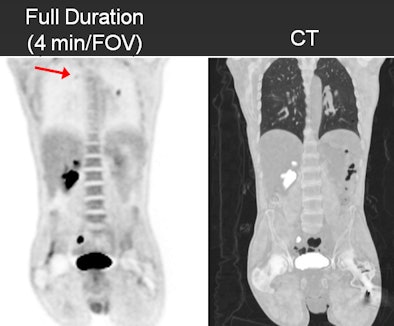

![]() |

| In these images of a 125-lb patient, the half- and full-duration studies had the same findings, whereas there was a false negative in the upper right lung on the quarter-duration scan. |

The analysis found that the one-minute and two-minute scans did not change staging in any patient, compared with the full-duration scan. The two-minute study had identical specificity to the full-duration scan and four false-negative results in two patients, who had a total of more than seven lesions. Sensitivity was 98%, with a specificity of 100%.

The one-minute study failed to detect lesions in 12 patients, compared with the full-duration scan. In total, it produced nine false positives and nine false negatives. Sensitivity was 91% and specificity was 93%.